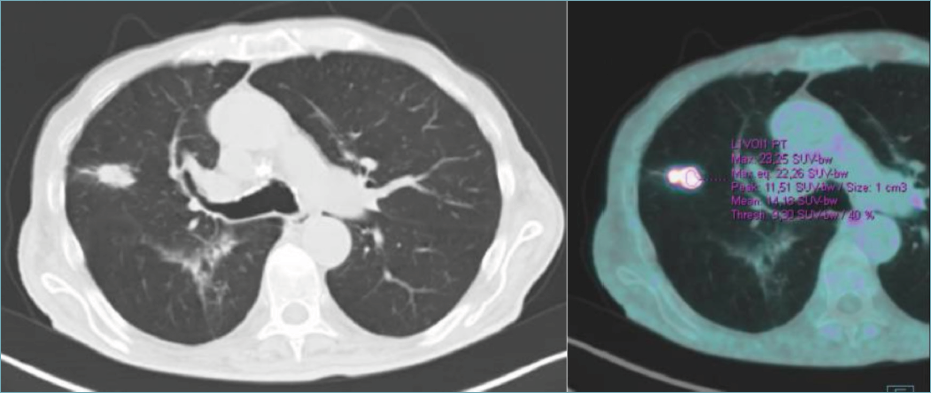

Histologically, the poorly differentiated adenocarcinoma accounted for two-thirds of the lesion, and unexpectedly, the remaining third was represented by a florid lymphoid infiltrate, with diffuse sheets of large, pleomorphic lymphoid cells, with prominent nucleoli, which destroyed and replaced the normal lung parenchyma (Fig. 3). The B-cell origin of the large cells was demonstrated by CD20 and CD79a staining (Fig. 4). The morphological and immunohistochemical characteristics satisfied the diagnostic criteria of pulmonary diffuse large lymphoma. The immunophenotype profiling (negativity for CD10 and the positivity for BCL6 and MUM1) was indicative of non-GCB histotype according to the Hans algorithm.

Figure 3. (A) The surgical specimen shows a well defined and circumscribed nodule. It is possible to appreciate two distinct areas, one with a lower cellularity (left) than the other (right). (B) At higher magnification, adenocarcinoma is seen on one side (left) and diffuse infiltrate of lymphoid cells on the other (right).

Figure 4. (A) The lymphoid infiltrate comprises diffuse sheets of large cells, which are 2-4 times the size of normal lymphocytes. (B) CD20 staining demonstrates the B-cell origin of the large cells.